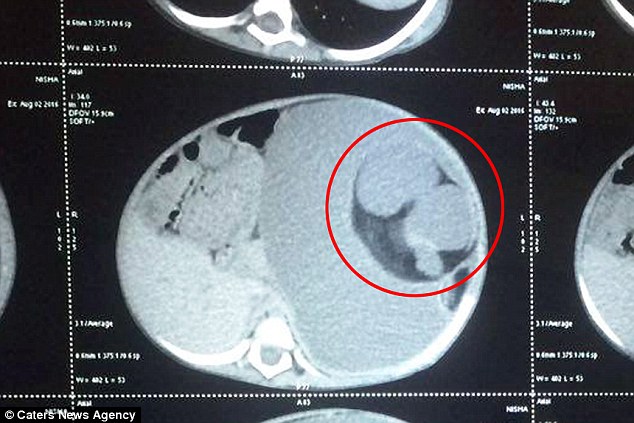

The doctors believed, at first sight, that the little girl definitely has a tumor in her abdomen, so they put her, after a few tests, directly in the operation. But the surgeon couldn’t believe what he found as soon as they cut the little girl. It wasn’t a tumor, it was her own twin brother.

This type of meal is called “parasitic brother” and had been attached to the girl’s stomach since her mother’s womb, feeding on the girl! The disease is also called “Fetus in fetus” and is very rare, there were only 200 such cases worldwide.

The mass that exists in these children usually has bones, muscles, and hair. The surgeons removed it from the girl’s stomach and then weighed her, she weighed over 3 kilograms, the weight of a baby at birth!

It seems that the operation was complicated by the fact that some organs of the face were joined with the organs of the parasitic twin, here is what the surgeon said: there were blood vessels all over the structure. So we had to remove blood vessels and move the organs, to separate them from the fetus, without damaging them ”.